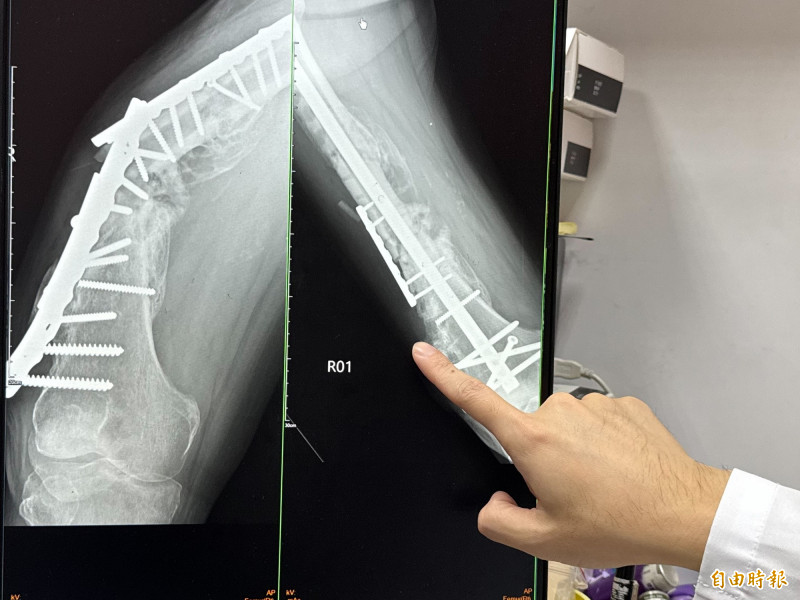

〔記者張軒哲/台中報導〕台中一名大甲媽祖頭旗隊的82歲王姓老翁,多年前在分送防疫物資時車禍被撞,導致大腿骨折,歷經兩次手術,原本使用鋼板固定,卻因金屬疲勞與體重無法支撐等多種因素導致鋼板斷裂而無法行走,日前進行第三次手術,骨科醫師將舊有的鋼板、鋼釘全部拆除,換上髓內鋼釘,讓骨頭重新癒合,手術一個月後,已經能行走站立,這名「勇腳伯」努力復健,明年再度參加繞境。

駐診在大甲李綜合醫院的台中榮總骨科主治醫師廖唯任表示,老翁當初大腿骨折斷成三截,手術治療後,卻因體重控制、血液循環不佳,再加上「大腿骨是全身上下最難愈合的部位」,導致內固定失敗,植入物斷裂、骨不癒合,讓患者不良於行無法正常走路。

王姓老翁說,自己擔任鎮瀾宮龍鳳繡旗隊副團長,每年都會跟隨9天8夜的遶境,無奈在車禍後走路不便,大腿經過這次重新裝設鋼板、鋼釘後,經過一個多月的復健,已經能逐漸站起來,「一定要努力復健,再跟著媽祖遶境。」